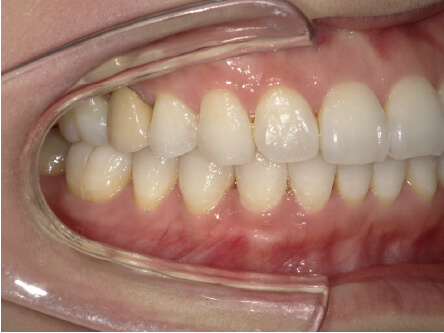

叢生の症例

8歳

女性

相談内容

前歯がでている、前歯が噛み合っていない

カウンセリング・診断結果

上下叢生、顎が狭いのでクリアコレクトで拡大配列+トレーニングで進めてく

治療内容・方法

全額アライナー矯正 クリアコレクト

術後の経過・現在の様子

リンガルアーチ使用

治療のリスク

痛み・歯根吸収・歯肉退縮・虫歯・後戻り

費用・治療期間

924,000円、8ヶ月